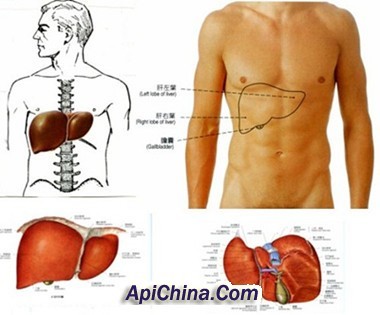

赘生物所附着的瓣膜有炎性反应及灶性坏死,其周边有淋巴细胞,纤维细胞及巨细胞浸润。坏死细胞周围有新生毛细血管,结缔组织及肉芽组织,当炎症消退,赘生物纤维化,表面为内皮细胞所覆盖,经治疗痊愈的病例,三个月才能完全愈合,未治愈的病例,愈合与炎症反应交叉存在。赘生物大而易碎,脱落可致脏器及周围动脉栓塞,如肾、脑、脾、肠系膜及四肢等,先心病并感染性心内膜炎病例,多并发肺栓塞,局部细菌滋长可使瓣叶产生溃疡或穿孔,腱索及乳头肌断裂及细菌性动脉瘤。抗原-抗体复合物在肾血管球沉积,可发生肾血管球性肾炎,由于免疫反应引起小动脉内膜增生,阻塞及小血管周围炎,表现为皮肤及粘膜的淤点,发生于手指、足趾末端的掌面,稍高于皮面,有压痛,5-15mm大小,称奥氏(Osler)结节,后掌及足趾有数毫米大小的紫红色斑点,称为Janeway氏结节。